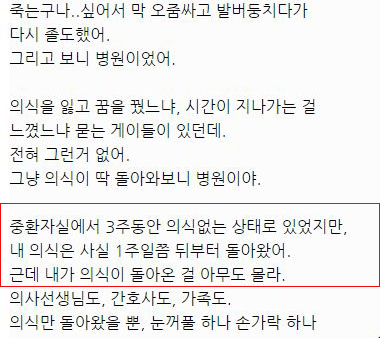

아래는 해당 글 작성자가 쓴 글.

대단한 얘기는 아니지만 중환자실에 3주동안 무의식으로 있었던 썰 풀어볼게